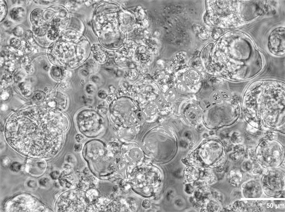

微环境对SC衍生β细胞成熟的影响的研究(Myungji et al., 2025)